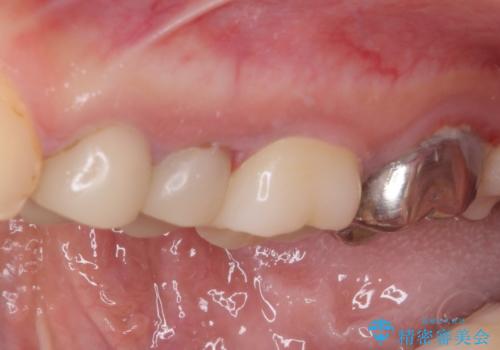

結婚式前に目立つ銀歯をセラミックに

- 笑ったときに見てしまう上顎奥歯の銀歯を気にして来院された患者様です。

折角セラミッククラウンを装着するので、根管治療を行った後に補綴治療を行うこととしました。

他にも目立つ銀歯がありましたが、最も気にしている2本を優先して行うこととしました。

結婚式前にはクリーニングやホワイトニングを行い、その後他の歯を治療していく予定です。